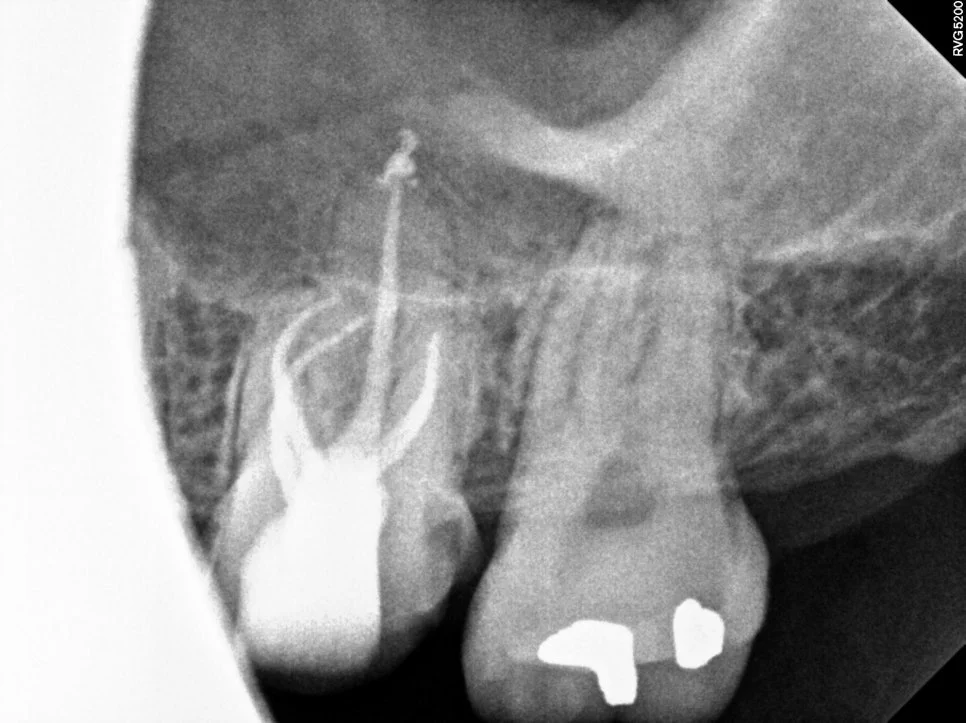

약간 다른 각도로 촬영해 보니 두 개의 신경관이 각기 다른 길로 주행하고 있습니다. 이런 치아에서 다른 하나의 신경관을 찾지 못했다면 신경치료 후 통증의 원인이 될 수 있습니다.

근관충전 결과

사진에 표기된 두 개의 신경관이 하나의 뿌리에서 각기 주행하는 다른 신경관입니다! 이렇듯 치아 내부의 신경관은 복잡하고 변이가 많아 신경치료를 모두가 어려워하는 실정입니다^^